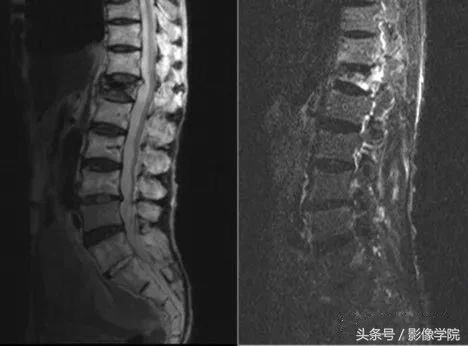

(2)MRI:可更准确地评估有无椎管压迫及骨折的新鲜程度,也是目前比较主要的检查。椎体内新鲜骨折所致的水肿表现为T2像和短T1反转恢复(STIR)序列信号增强及T1像信号减弱。一定要拍脂肪抑制像,以鉴别是否为新鲜骨折、肿瘤或是椎体内脂肪岛。

病例演示:老年女性患者,轻微外伤后出现胸背部疼痛不适

MRI提示胸12椎体新鲜骨质疏松性压缩骨折,诊断明确后局部麻醉下行经皮椎体后凸成形术(PKP)